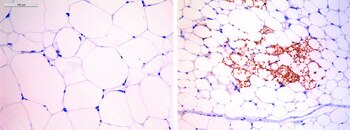

Lo han logrado en el Centro Nacional de Investigaciones Oncológicas (CNIO), donde los científicos han comprobado que la administración de ese fármaco (la digoxina) hizo que los animales perdieran hasta el 40 por ciento de su peso, comiendo incluso una dieta rica en grasa, y que se curaran de los trastornos metabólicos asociados a la enfermedad.

El CNIO ha observado que la obesidad es una enfermedad inflamatoria, una reacción defensiva crónica del organismo ante la agresión que supone el exceso de nutrientes, y a partir de esa premisa los científicos se propusieron combatirla evitando la inflamación.

La "digoxina" actúa reduciendo la producción de una molécula que es la que generalmente provoca la inflamación y los investigadores han descubierto que esa molécula interviene directamente en el tejido adiposo, causando la obesidad y las alteraciones metabólicas graves asociadas al sobrepeso, como la diabetes tipo 2, la hipertensión o las enfermedades cardiovasculares, además de aumentar el riesgo de padecer cáncer.